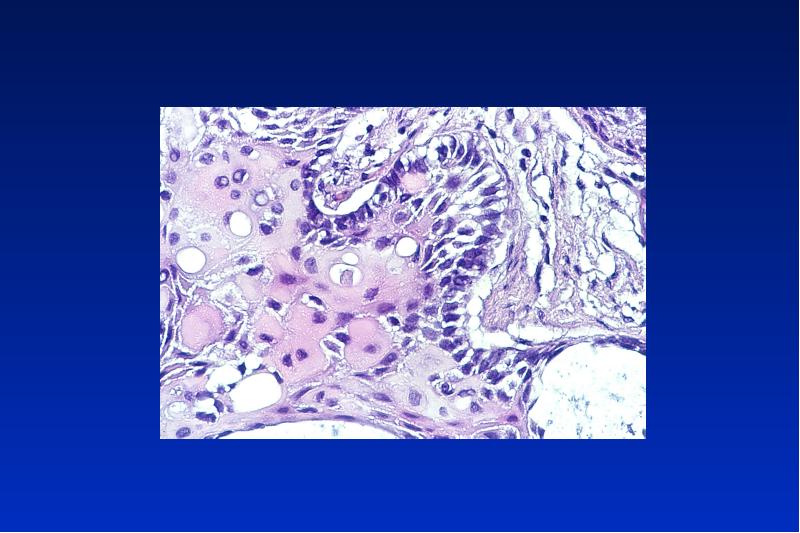

- 56. Odontom complex = gemischt compound

- 59. Kalzifizierende odontogene Zyste Odontogener Ghost cell Tumor zystisch oder solid gebaut